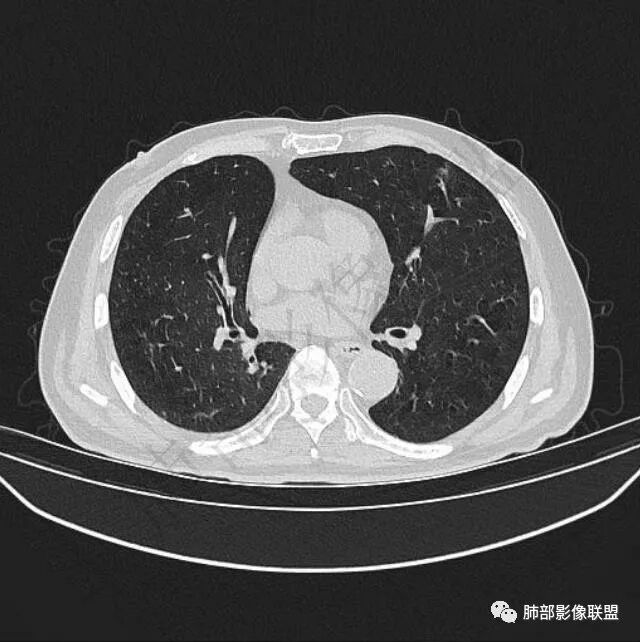

再1个多月后病灶继续增大,较明显不均匀强化,肺门一侧见低密度区。病灶边缘相对不清,可见毛刺。

三.病程脉络相当清楚,即病灶进行性增大,易想到新生物或转移瘤,但经验上分析增长速度显然太快,尤其是对于原发肺腺癌或者肺鳞癌而言,单发转移瘤也较少这样的进展速度。

四.单就影像而言,病灶肿瘤特征不够充分,恶性肿瘤病史,隐球菌等特殊感染确实不能排除。

五.尽管本例鳞癌的病例意见出乎预料,但部分低分化肿瘤迅速增长也不时出现,仍须警惕!